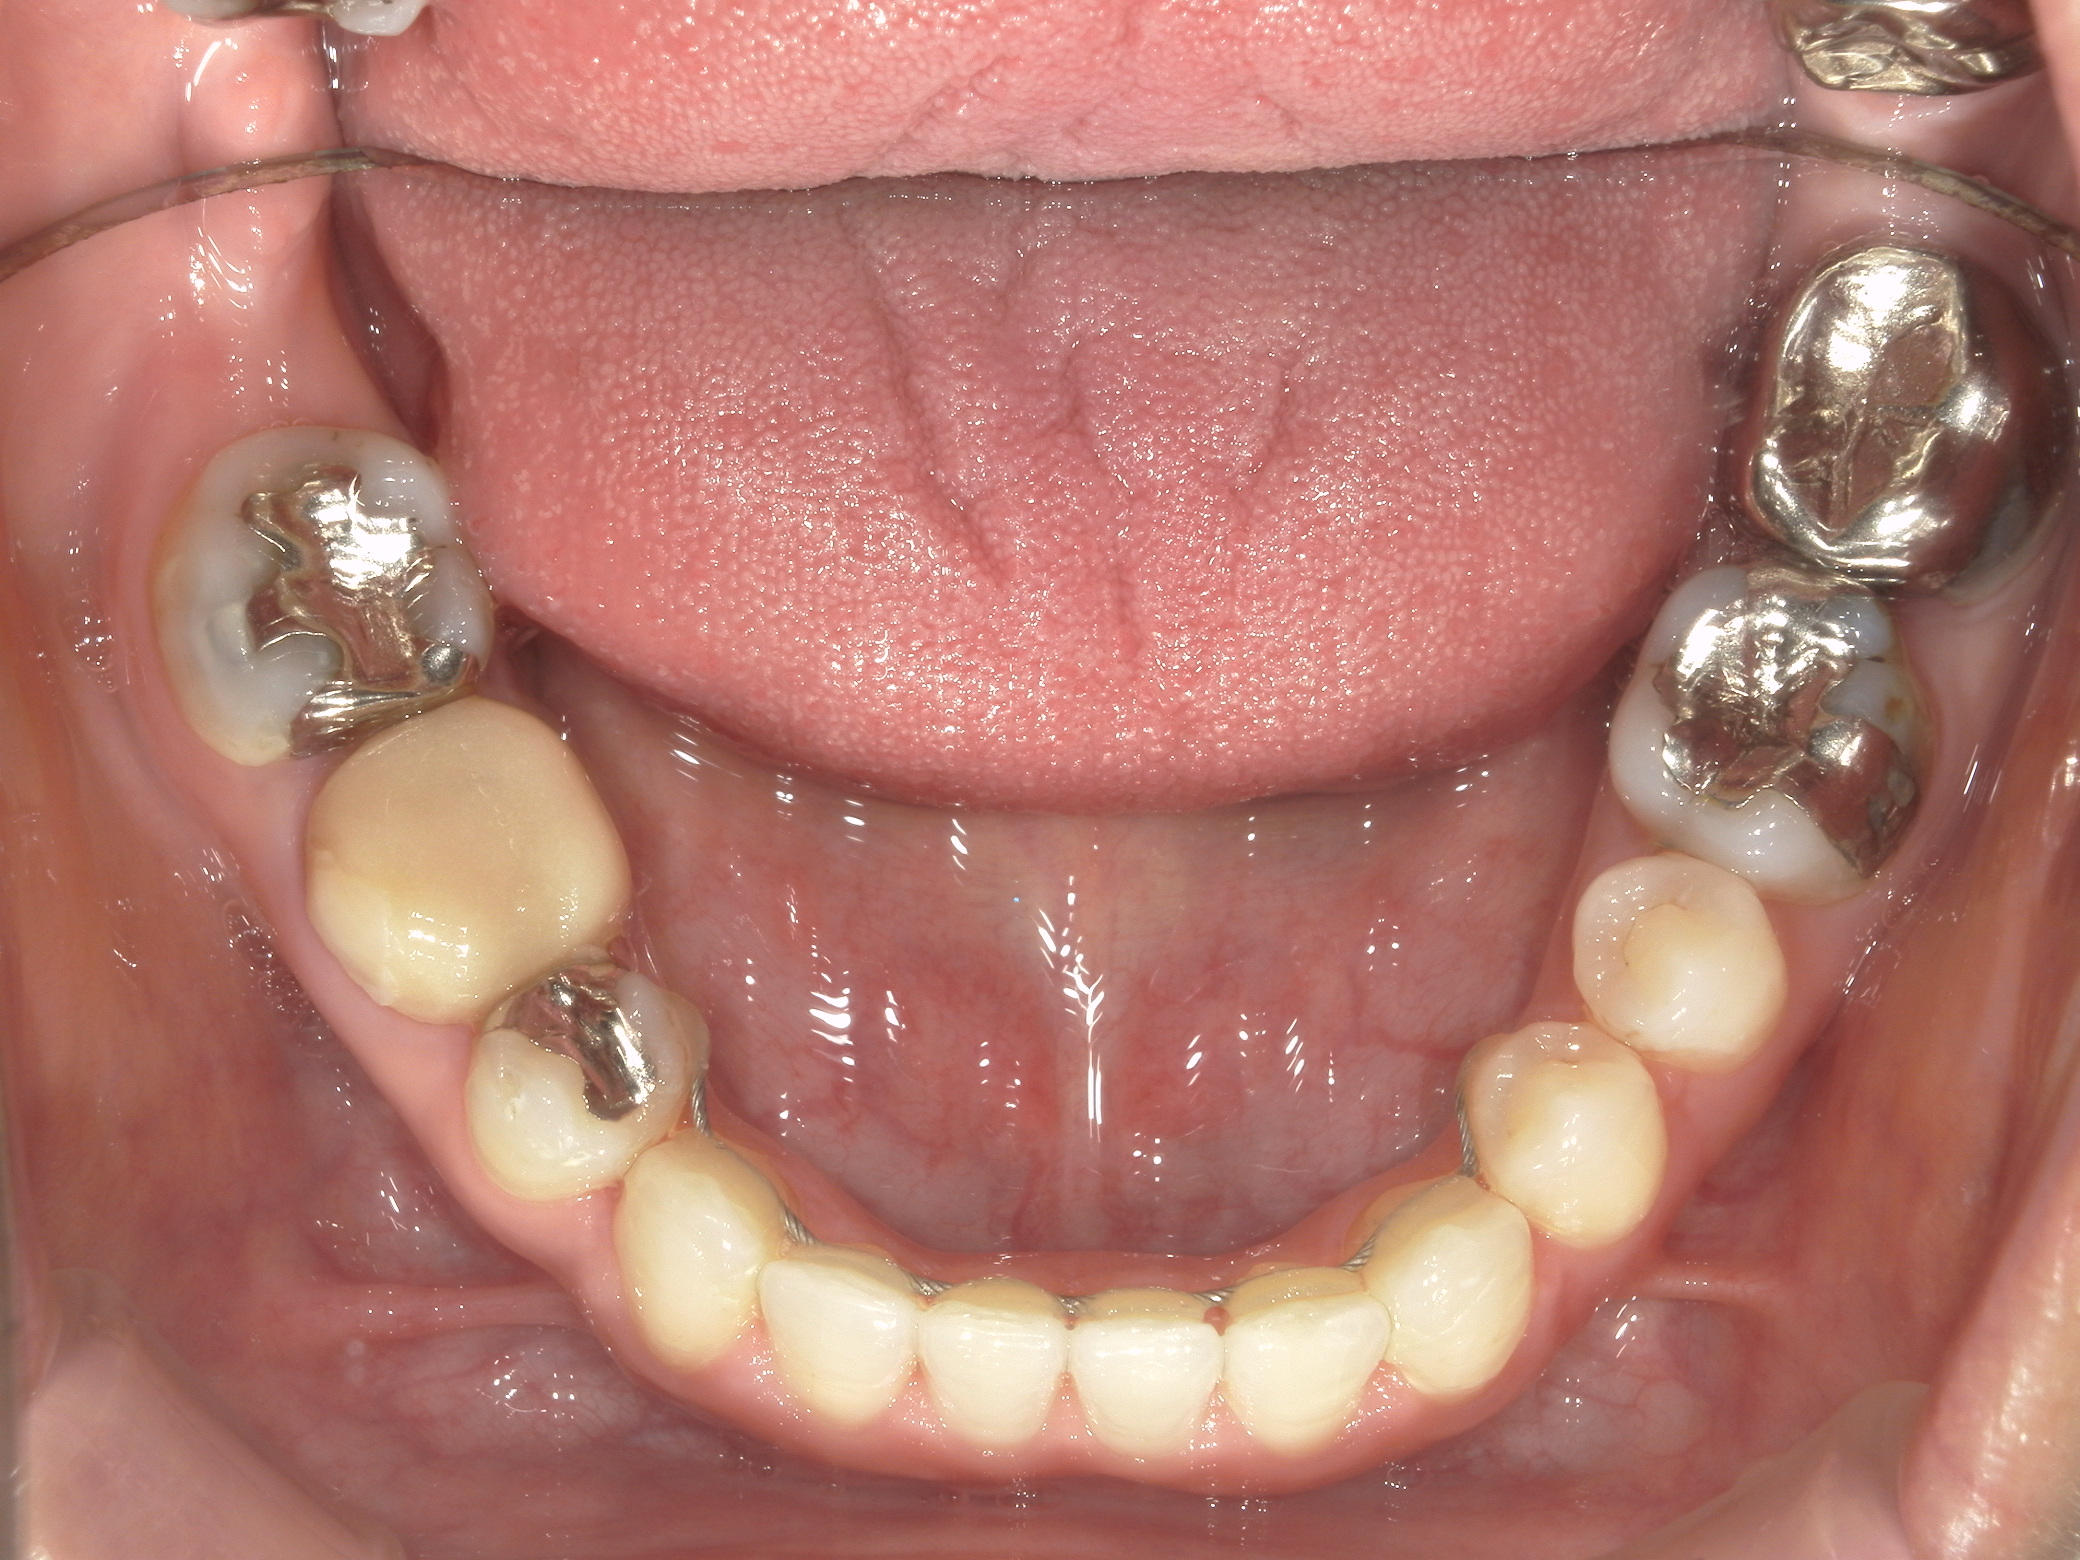

右下第一小臼歯(1本)、右下親不知(1本)を抜歯。

右下第一大臼歯をセラミックへ変更。

③矯正装置を除去し、インビザライン矯正で歯列を整えました。